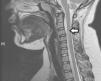

Niña de 10 años con fiebre de 39°C, parestesias, dolor en hombro derecho, cervicalgia e impotencia funcional y pérdida de fuerza de miembros superiores (MMSS) de 24h de evolución. En la exploración muestra debilidad proximal de la cintura escapular de predominio izquierdo 1/5 (derecha 2/5) y fuerza distal conservada (4/5), requiriendo sondaje por retención urinaria. Presenta cultivos (hemo y urocultivos), serologías, estudio de inmunidad, citoquímica y bandas oligoclonales en LCR, todos negativos salvo IgM e IgG positivas para virus varicela zoster (VVZ), indicativo de infección previa no activa, refiriendo en ese momento la madre que la paciente había presentado varicela un mes y medio antes, no siendo posible determinar la PCR a VVZ en LCR. La RM descarta alteración craneal y evidencia aumento del calibre medular y lesión fusiforme hiperintensa en T2 que afecta a la porción anterior y periférica de la médula en C3-C4 sin captación de contraste compatible con etiología varicelosa (fig. 1).

El diagnóstico de mielitis posvaricelosa se realiza mediante serología plasmática, PCR de VVZ en LCR y RM, donde es característica la inflamación medular con imágenes fusiformes hiperintensas en T2 y realce heterogéneo, así como la afectación de varios niveles vertebrales, tal y como se observa en nuestro caso2,5.